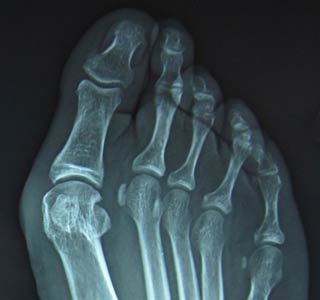

How Wide Toe Box Shoes Can Help or Prevent Bunions

Take a look at our foot health blog about bunions where we explore causes and treatments of bunions including the health benefits of wide toe box shoes.